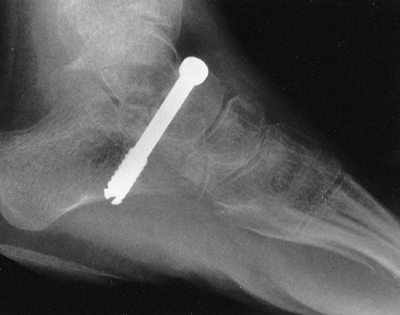

Figure 15.1

Radiographs showing substantial changes in the right hip, including

dislocation, which developed in a 10-year-old child over a period of a

few months. Annual hip evaluations, including radiographs, are

important for detecting such problems. -